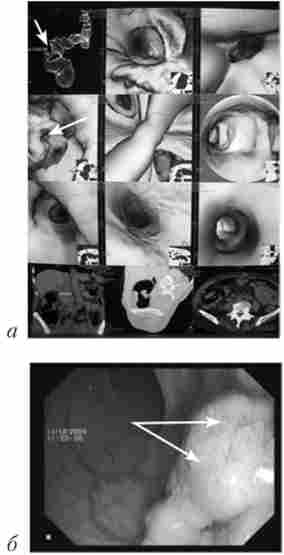

Основним методом рентгенологічного дослідження товстої кишки служить іригоскопія (Рис. 14.5). Вона полягає в ретроградним введенні контрастної речовини через пряму кишку за допомогою апарату Боброва, що дозволяє домогтися тугого наповнення органу і детально вивчити положення, форму, розміри і особливості контуру товстої кишки. При цьому також використовують метод подвійного контрастування, т. Е. Другою

етап ирригоскопии. Другий етан виконується після спорожнення кишки від ренгеноконтрастной суспензії. Дослідження проводять при дозованому заповненні кишки повітрям, також використовуючи апарат Боброва. На тлі подвійного контрастування стає можливим детальне вивчення рельєфу слизової оболонки.

Рентгенологічна картина раку ободової кишки

Мал. 14.5. Рентгенологічна картина раку ободової кишки

(Іррігограмми):

а - стрілками вказано дефект наповнення; б - стрілками вказано ділянку циркулярного звуження просвіту кишки

Інтерпретація рентгенологічної картини заснована на тих же принципах, що і аналіз результатів рентгенологічного дослідження стравоходу, шлунка і дванадцятипалої кишки із застосуванням перорального контрастування. При раку ободової кишки виявляють ділянки звуження товстої кишки, визначають «ніші», дефекти наповнення, зміни рельєфу слизової оболонки і оцінюють рухову активність кишки.

Мал. 14.6.

Фіброколоноскопія. Рак ободової кишки

Фіброколопоскопія (ФКС) - в даний час це основний метод діагностики раку ободової кишки (рис. 14.6). Фіброколопоскопія є огляд слизової оболонки товстої кишки за допомогою спеціальних гнучких ендоскопів з волоконної оптикою. З метою морфологічної верифікації пухлини під час колопоскопіі може бути виконана прицільна біопсія слизової оболонки.

В останні роки для діагностики пухлин ободової кишки застосовують так звану віртуальну колопоскопію. Вона являє собою комп'ютерне томографічне дослідження ободової кишки після попереднього її заповнення повітрям. Відмінність отриманих результатів від результатів класичної КТ в тому, що програмне забезпечення на підставі одержуваних з датчиків даних будує тривимірну модель кишки, дуже схожу на картину, видиму в звичайний фіброколоноскон (рис. 14.7).

Дане дослідження значно легше переноситься хворими в порівнянні з оптичною ФКС. Але діагностичні можливості методу менше, ніж у оптичної ФКС: поліпи розміром менше 1 см видно не завжди.

Колоноскопія поліпа ободової кишки

Мал. 14.7. Колоноскопія поліпа ободової кишки:

а - віртуальна; б - оптична